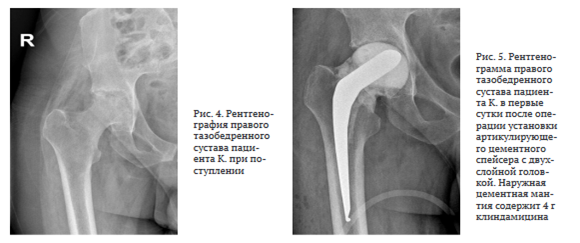

Антибактериальную терапию на амбулаторном этапе не получал. Поступил в НМИЦ ФПИ с жалобами на боль в левом тазобедренном суставе, передвигался при помощи костылей. Функциональные показатели сустава по шкале HHS — 35, по шкале WOMAC — 79, выраженность болевого синдрома по шкале ВАШ — 7 баллов. На КТ левого тазобедренного сустава определена деструкция верхнего фрагмента головки левой бедренной кости без признаков контактной деструкции вертлужной впадины, сужение суставной щели (рис. 1).

Иммунологические исследования: CD-4 = 551 кл/мкл, ВН в крови < 20 копий/мл. Лабораторные исследования: отклонение от рееференсных значений: СОЭ — 36 мм в час, лейкоциты — 2,41*109, С-реактивный белок — 4,5 мг/л. 07.03.2023 под лучевым контролем выполнена трепанобиопсия области очага костной деструкции в головке бедренной кости.

Микробиологическое исследование биоматериала: получена культура Acinetobacter baumanii (чувствительность к гентамицину), Staphylococcus capitis (чувствительный ко всему спектру антибиотиков). Патогистологическое заключение: признаки хронического неспецифического коксита. Пациенту установлен диагноз: неспецифический коксит слева, ассоциированный с ВИЧ-инфекцией.

Перед оперативным лечением по назначению клинического фармаколога проведен курс комбинированной антибактериальной терапии: меропенем 2000 мг 3 раза в сут. в/в, амикацин 1000 мг 1 раз в сут. в/в в течение 15 дней. 27.03.2023 проведена резекция головки левой бедренной кости, установка артикулирующего двухслойного спейсера с гентамицином (4 г) (рис. 2). ПЦР операционного материала от 28.03.2023: ДНК микробактерии туберкулеза (МБТ) не обнаружена. Послеоперационный период протекал без осложнений.